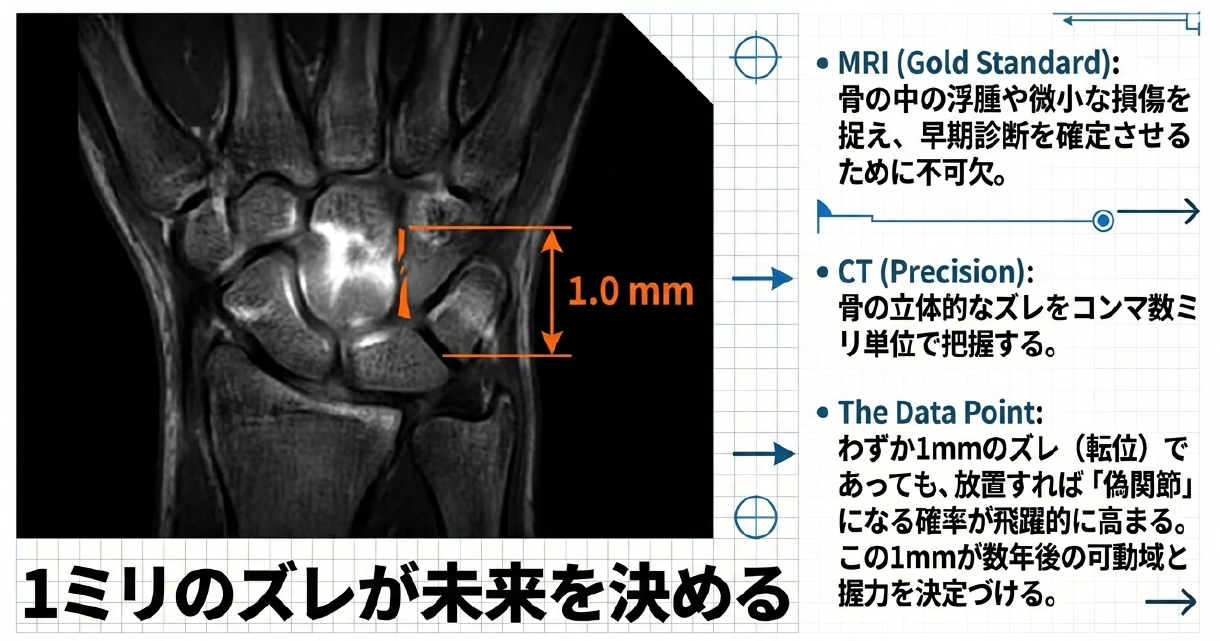

近年、この「見えない骨折」を炙り出すために、MRIやCTといった高度な画像診断が不可欠となっています。特にMRIは、骨の中の浮腫や微小な損傷を捉える能力に長けており、受傷後早期の診断においてゴールドスタンダードとしての地位を確立しました。また、CTは骨の立体的なズレをコンマ数ミリ単位で把握するために用いられます。科学的なデータによれば、わずか1ミリのズレ(転位)であっても、それを放置すると骨がくっつかない「偽関節」になる確率が飛躍的に高まることが示されています。アスリートにとって、この1ミリを見逃すかどうかが、数年後の手首の可動域や握力を決定づけるのです。